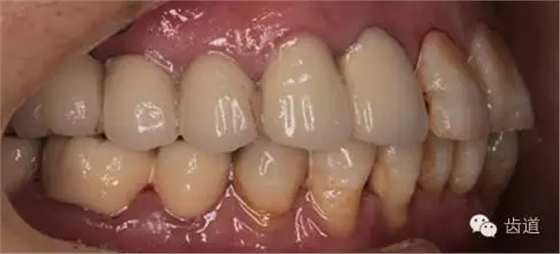

1、全口正面觀

5、右下頜側(cè)面觀

2、治療后